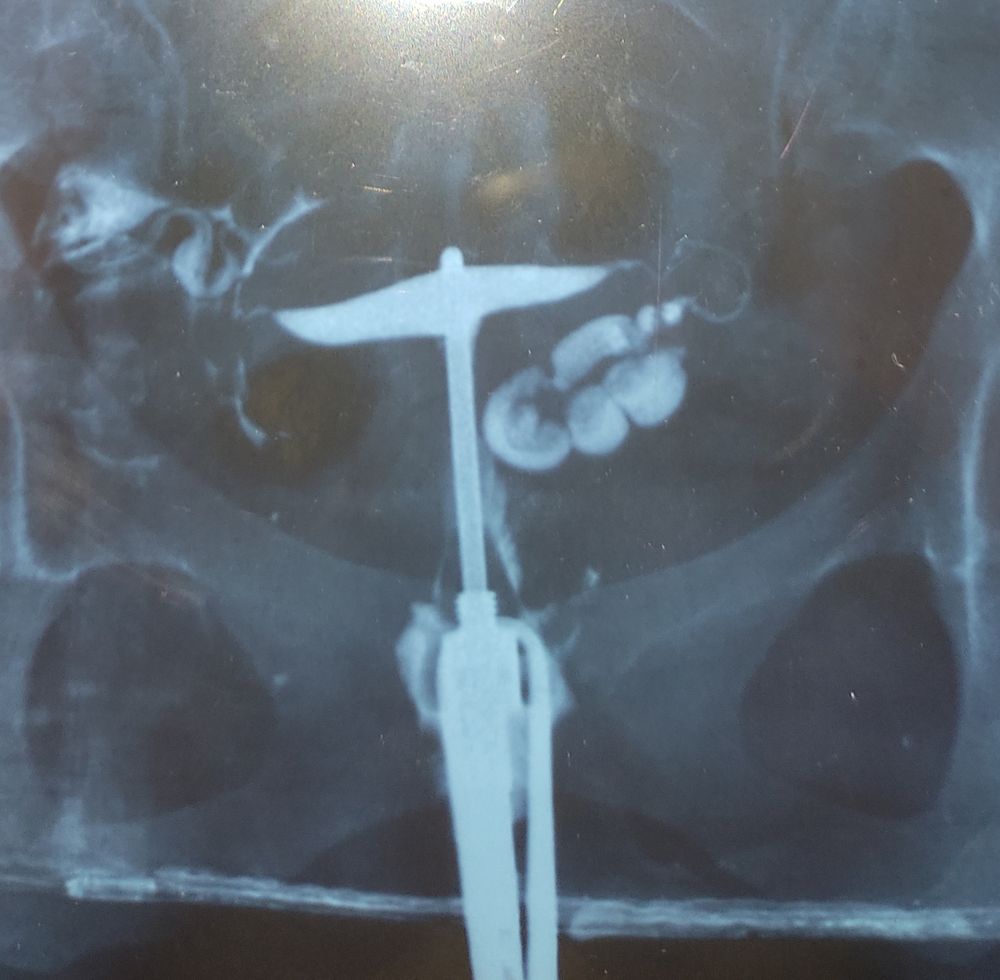

Надумала выложить фото с ГСГ. В заключении: правая труба проходима. Левая в виде гидросальпинкса в "... " отделе. Сейчас лень искать в этой кипе бумаг

Съездила забрала снимок с результатами: правая проходима. Левая в виде гидросальпинкса. Интернет. Паника. Понимание что нужна лапара и чем раньше, тем лучше.

Начала я своё обследование с ГСГ.